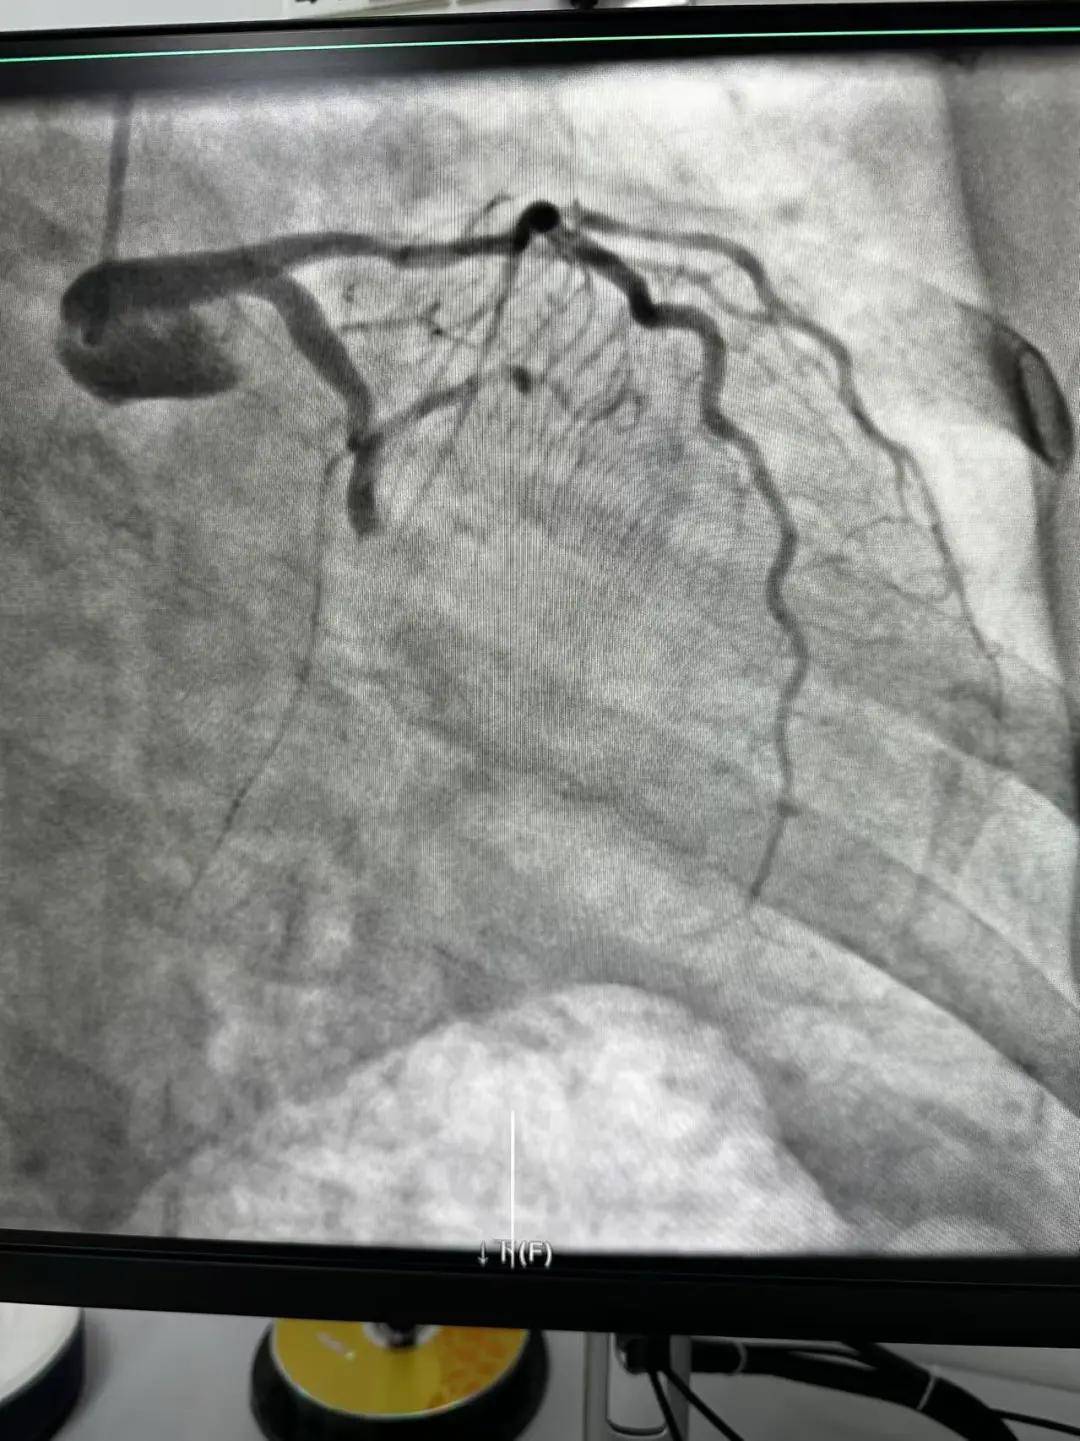

今天最后一臺手術(shù),是一個嚴重三支病變的病人,患者張大爺,71歲,以“突發(fā)胸悶胸痛3小時”為主訴入院。經(jīng)心電圖檢查后示室上性心動過速,以“冠心病、心絞痛、心律失?!睘樵\斷收住入心內(nèi)科。心內(nèi)科團隊通過審慎評估,決定給予患者冠狀動脈造影術(shù)及冠狀動脈內(nèi)支架置入術(shù)。

許先生,52歲,大貨司機,在鶴壁至安陽卸貨過程中,突發(fā)胸悶胸痛,伴大汗1.5小時。 患者繞行安陽,于11點38分到達我院大門,11點41分首份心電圖,提示患者下壁心肌梗死。 起病急,病程短,情況十分危險,如果血管完全堵塞將直接威脅患者生命,亟需疏通堵塞血管進行血運重建。

穿刺、造影、放支架……兩個手術(shù)間各個環(huán)節(jié)緊張卻有序地進行著!在心內(nèi)科團隊精準、默契的配合下,兩臺手術(shù)順利完成! 兩名患者的快速、同時、成功救治,得益于殷都區(qū)人民醫(yī)院醫(yī)務(wù)人員快速的應(yīng)急能力、過硬的急救技能,同時更得益于導(dǎo)管室同開臺,保障了救治的迅速有效。